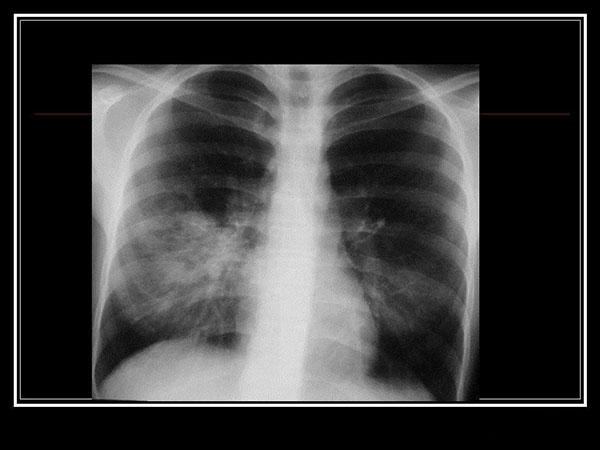

Основа диагностики – инструментальные и лабораторные методы исследования. Рентген показывает слабые либо среднеинтенсивные участки инфильтрации в виде размытых теней, усиление бронхиального и сосудистого рисунка.

Симптомы атипичной пневмонии у взрослых и детей малоспецифичны. Диагноз в основном подтверждается при исследовании биологического материала пациента, который направляется на исследование сразу же, как только врачу становится понятно, что классический протокол лечения эффекта не даёт. Во многих случаях на рентгенологическом снимке просматривается воспалительный процесс в лёгких, но стандартная терапия никакого эффекта не даёт.

Врач может распознать микоплазменную пневмонию на рентгеновском снимке. Лечение проводится медикаментозное, преимущественно макролидами и тетрациклинами.

Атипичная микоплазменная пневмония на снимке